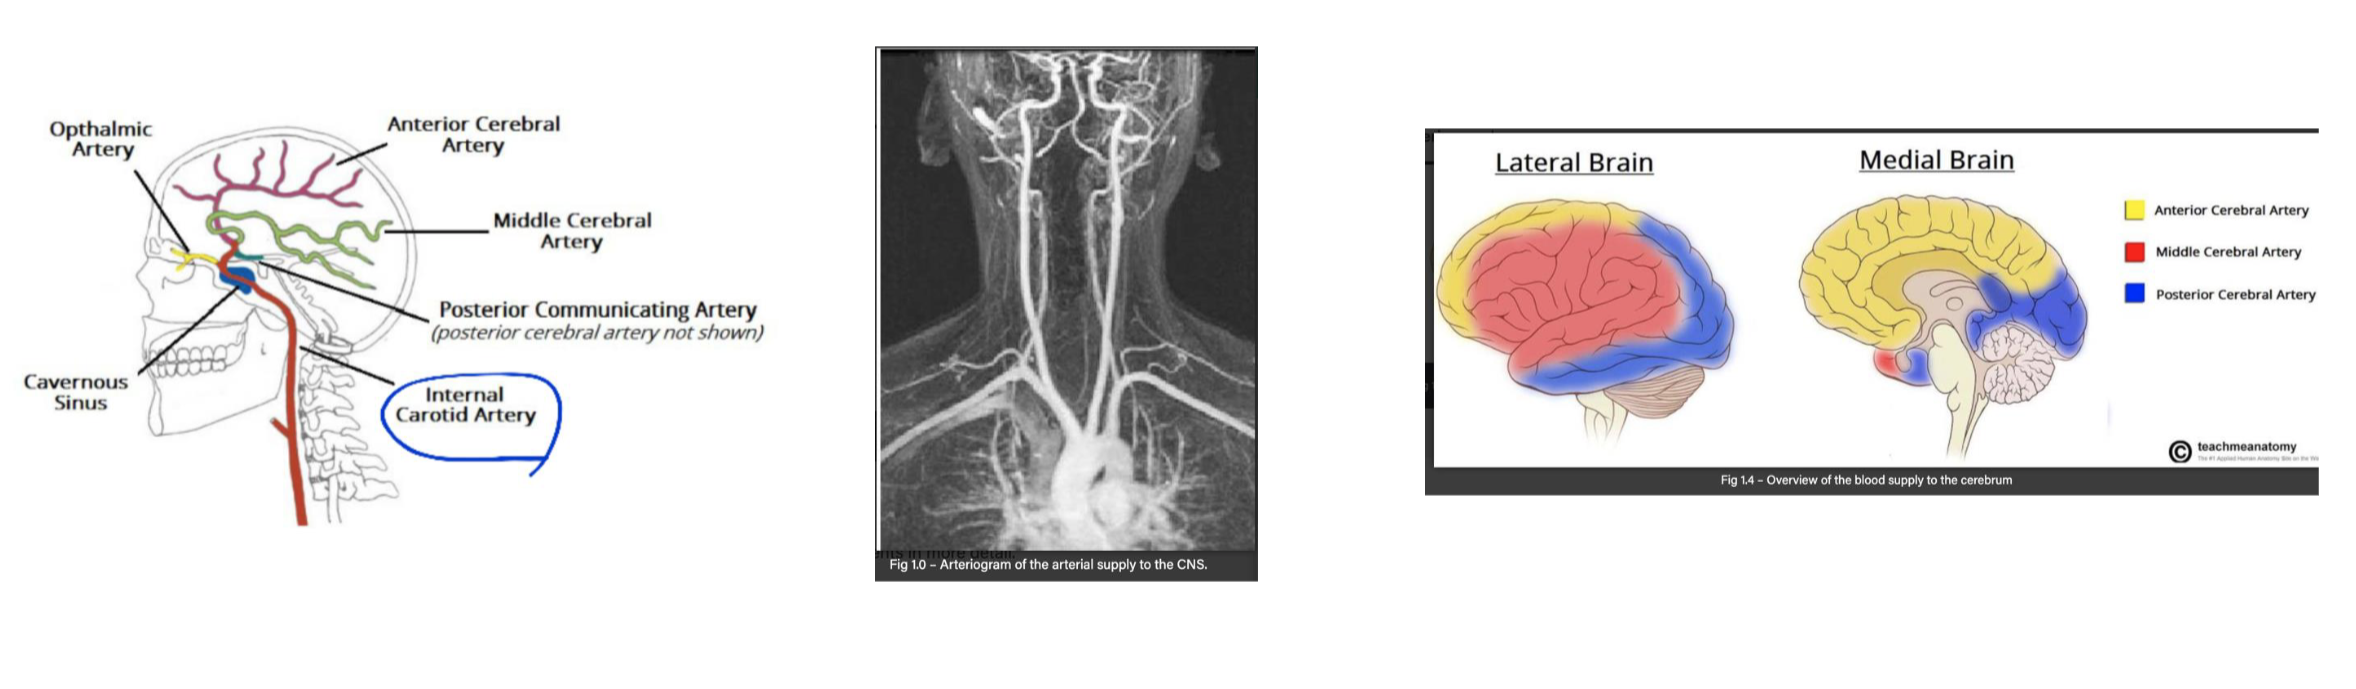

Vasculature

Arteries - Large vessels that carry oxygenated blood from the heart to the rest of the body, including the brain

Arterioles - Small arteries

Capillaries - Very small, thin walled vessels where oxygen is extracted

Veins - bring deoxygenated blood back to the heart